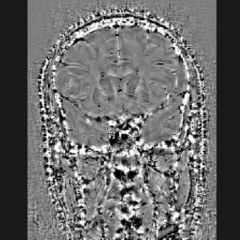

Une cartographie du fer cérébral robuste et performante

Le fer cérébral joue un rôle clé dans de nombreuses pathologies neurologiques, mais sa quantification reste complexe et débattue.

Les techniques d’imagerie conventionnelles fournissent peu de précision sur sa distribution fine.

Nos solutions permettent de cartographier le fer in vivo, offrant des mesures fiables et reproductibles pour explorer son implication dans la neurodégénérescence.